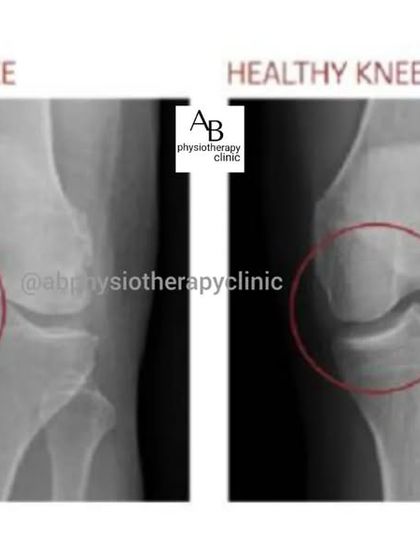

- Arthritis and joint stiffness (Osteoarthritis, Rheumatoid, all of it)

- Maitland or Mulligan mobilization concepts for frozen shoulders or osteoarthritis.